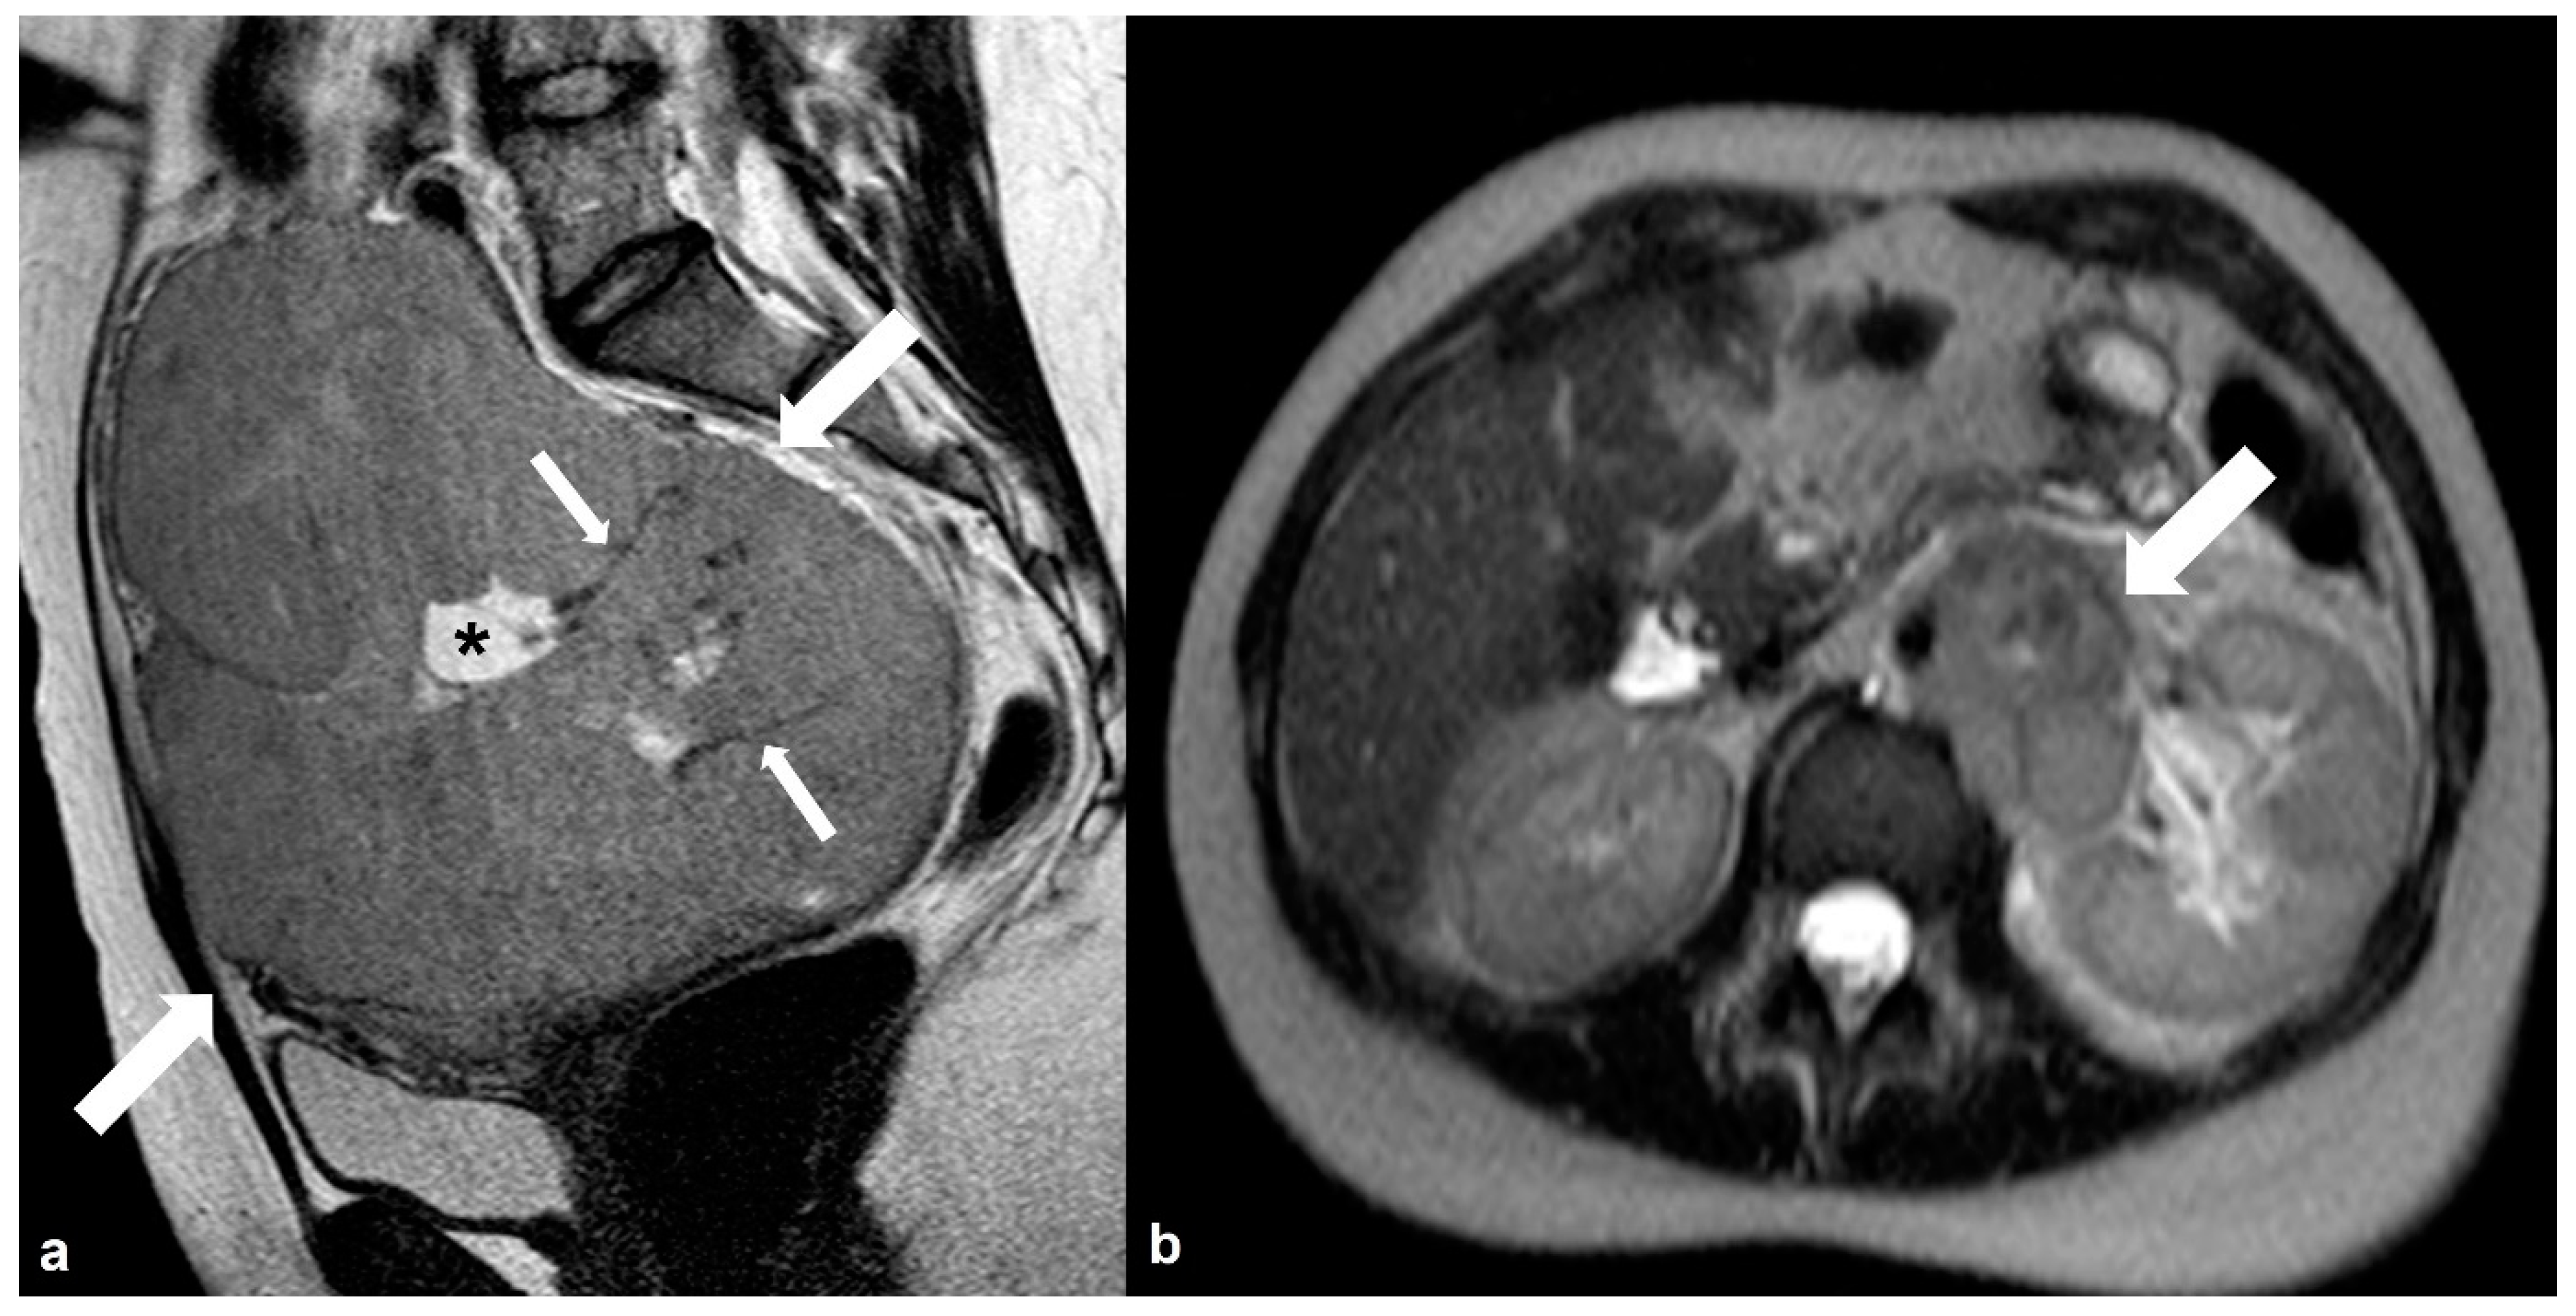

2.6.1. Mucinous Rectosigmoid Cancer

2.6.2. Appendiceal Mucocele—PMP